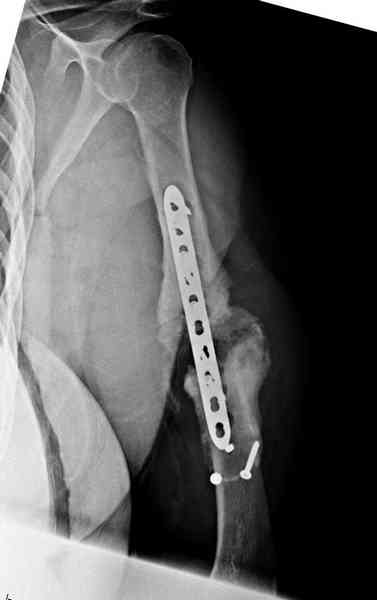

Помогите, пожалуйста, определиться с тактикой!Поступил больной с ложным суставом плечевой кости... Перелом был 2 года назад. Лечился в аппарате 8 месяцев, консолидации не произошло. В феврале 2007 выполнена костная аутопластика, фиксация пластиной (на базе одной из ИК). Сейчас сохраняется ложный сустав, плечо укорочено на 3 см, контрактура обоих смежных суставов, атрофия мышц плеча и плечевого пояса справа. Явлений остеомиелита не отмечалось. Больной - осужденный, сидеть ему до 2012 года.

Уважаемая Татьяна,

Как видно из выступлений коллег, способы фиксации

ложного сустава плеча могут быть различными, кто-то предпочитает аппаратом Илизарова (Соломин), пластинами (Волна) или интрамедуллярным гвоздем (Челноков).

Когда разбирался случай на сайте, и у нас была больная с похожей патологией, ложный сустав после поперечного перелома, леченного год назад где-то и кем-то в другом месте.

Мы не стали делать провокационный метод, который

предложил Корнеев для лечения - применение анаболических стероидов - ретаболила, из-за его бессмысленности, также не согласились с его теорией, что любая операция заблокирует суставы, а наоборот, провели жесткую фиксацию пластиной для раннего восстановления.

Первичную пластину убрали недели 6 назад из переднего оригинального доступа, и из-за подозрительности тканей вокруг пластины, решили провести реконструкцию поэтапно.

После промывки и дебридмента для уверенности уложили антибиотический цемент. Культура из раны в последующем была отрицательная.

Хотя сам не стороннник применения более массивных

имплантов для плеча, но для этого случая сделали

исключение. На снимке 4А диаметр мягких ткани около 20 см, при весе больной более 135 кг, и также выступление Андрея Волны подстегнуло к применению более массивной 4.5 мм локинг пластины.